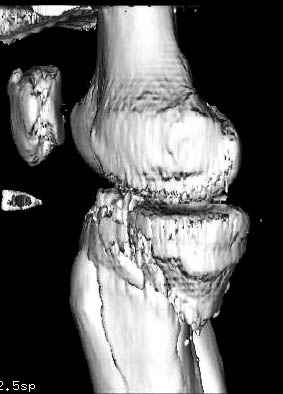

Пациенту сделали КТ - ухитрились сделать на шине Белера (не давал положить прямую ногу) - срезали передний отдел. Планируется на пятницу (24.12) на операцию - синтез длинной мыщелковой LCP-пластиной Synthes :). Отек ближе к слову умеренный (окружность голени +4 см по сравнению со здоровой). КТ и снимок на вытяжении прилагаются.

Трудно поверить, что разрекламированная Ортопедическая школа Восточной Украины позволяет такие странные снимки? На прямом снимке сохранен общий контур плато, но не известна судьба импрессии суставной поверхности. На полубоковой?, оставлен без репозиции задне-медиальный отдел, и навряд ли после такой фиксации можно удовлетвориться результатом.

Здесь как раз тот случай, когда результат зависит не только от мастерства хирурга, но и от наличия современных методов исследования. Например, КТ которая поможет рассчитать направления шурупов и установку импланта. Кроме этого, поможет определиться с доступом.

На представленных предоперационных срезах КТ огромный задне-медиальный фрагмент расположен больше кзади, чем медиально. Для планирования, кроме поперечных срезов, надо ориентироваться на корональные срезы, которые укажут топографию верхушки медиального фрагмента.

Надеюсь, представленные снимки разных случаев помогут разобраться в тактике, и критика примется без личной обиды.